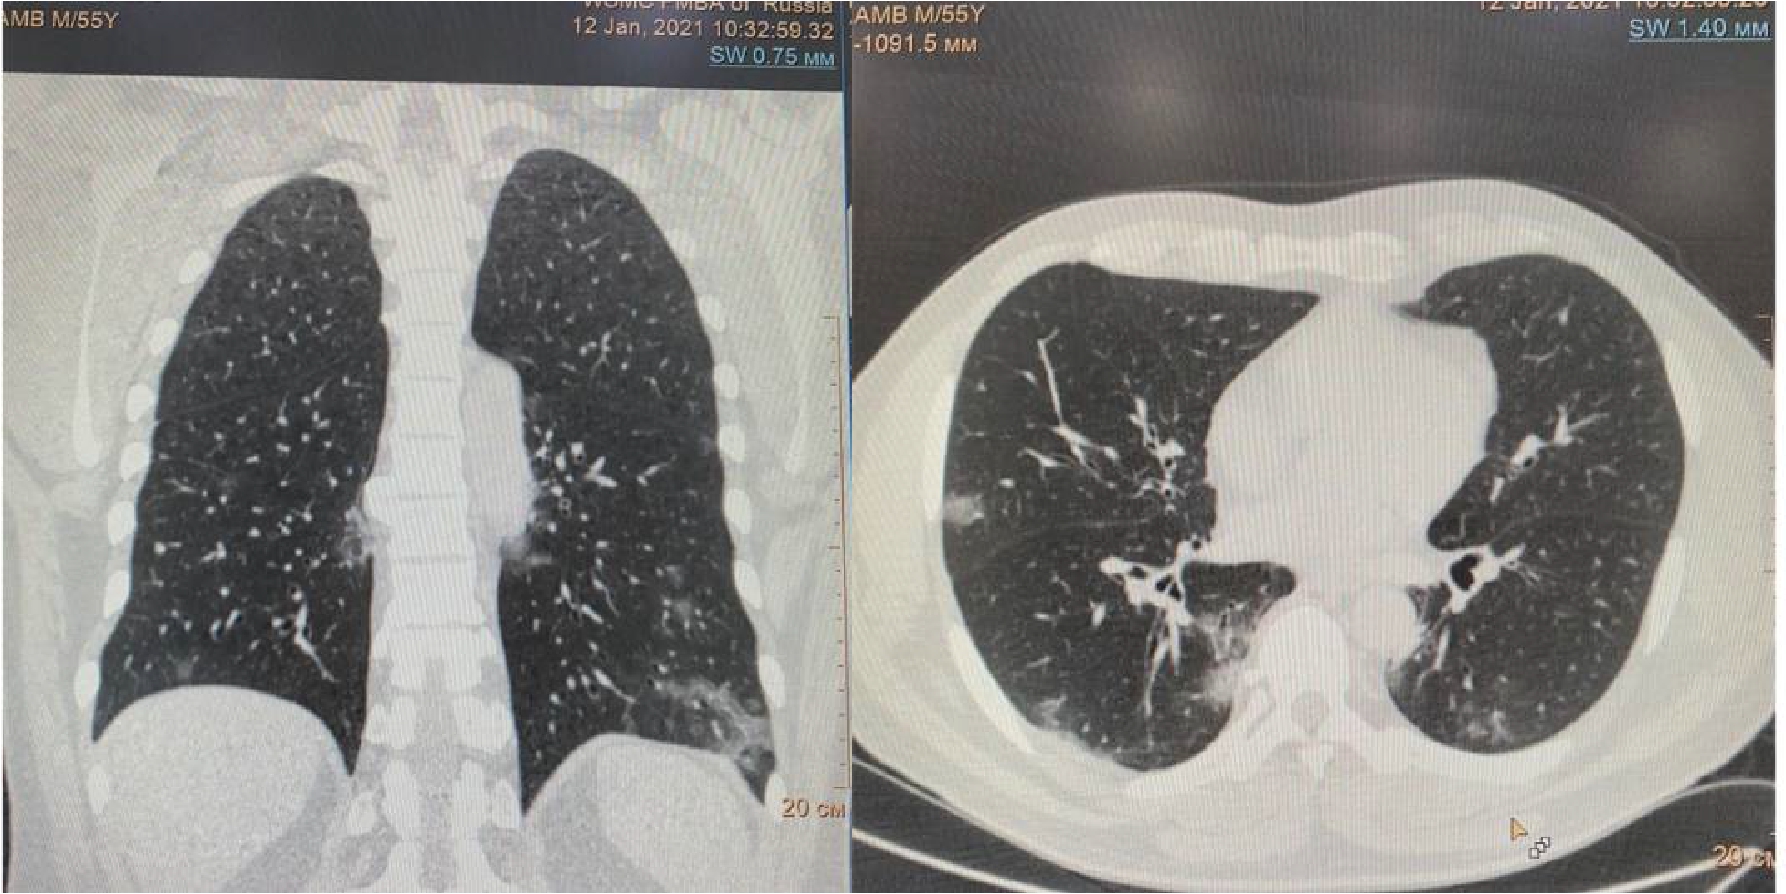

Рисунок 2. МСКТ органов грудной клетки – признаки двусторонней полисегментарной интерстициальной пневмонии (объем поражения 40%, КТ-2)

На 4-е сутки госпитализации выявлено ухудшение клинического статуса (снижение SpO2 до 93%, температура тела более 38 0С), отрицательная динамика по МСКТ (объем поражения 28%, КТ-2, в связи с чем к лечению добавлен олокизумаб однократно, без отчетливого клинического эффекта. На 7-е сутки госпитализации МСКТ выявила дальнейшее прогрессирование поражения легких (объем поражения 40%, КТ-2 (рис.2) на фоне сохранения умеренно выраженного кашля (со скудной мокротой), нарастания дыхательной недостаточности (SpO2 85-88% без инсуффляции кислорода). Больной переведен в отделение анестезиологии и реанимации, где находился в течение 3 суток, лечение включало преднизолон 480 мг/сут (начальная доза), противокашлевый препарат центрального действия (бутамират), проведен плазмоферез (аппарат Fenwal; инфузия плазмы - 2440 мл, эксфузия плазмы - 1430 мл) с введением антиковидной плазмы (270 мл).

На 16 сутки госпитализации пациент начал жаловаться на резкое усиление одышки даже в покое, невозможность находиться в прон-позиции. МСКТ органов грудной клетки обнаружила уменьшение объема поражения легких до 30%, также был впервые выявлен спонтанный средний правосторонний пневмоторакс (рис. 3).

Рисунок 3. МСКТ органов грудной клетки – признаки двусторонней полисегментарной интерстициальной пневмонии (объем поражения 30%, КТ-2). Средний правосторонний пневмоторакс (красные стрелки).